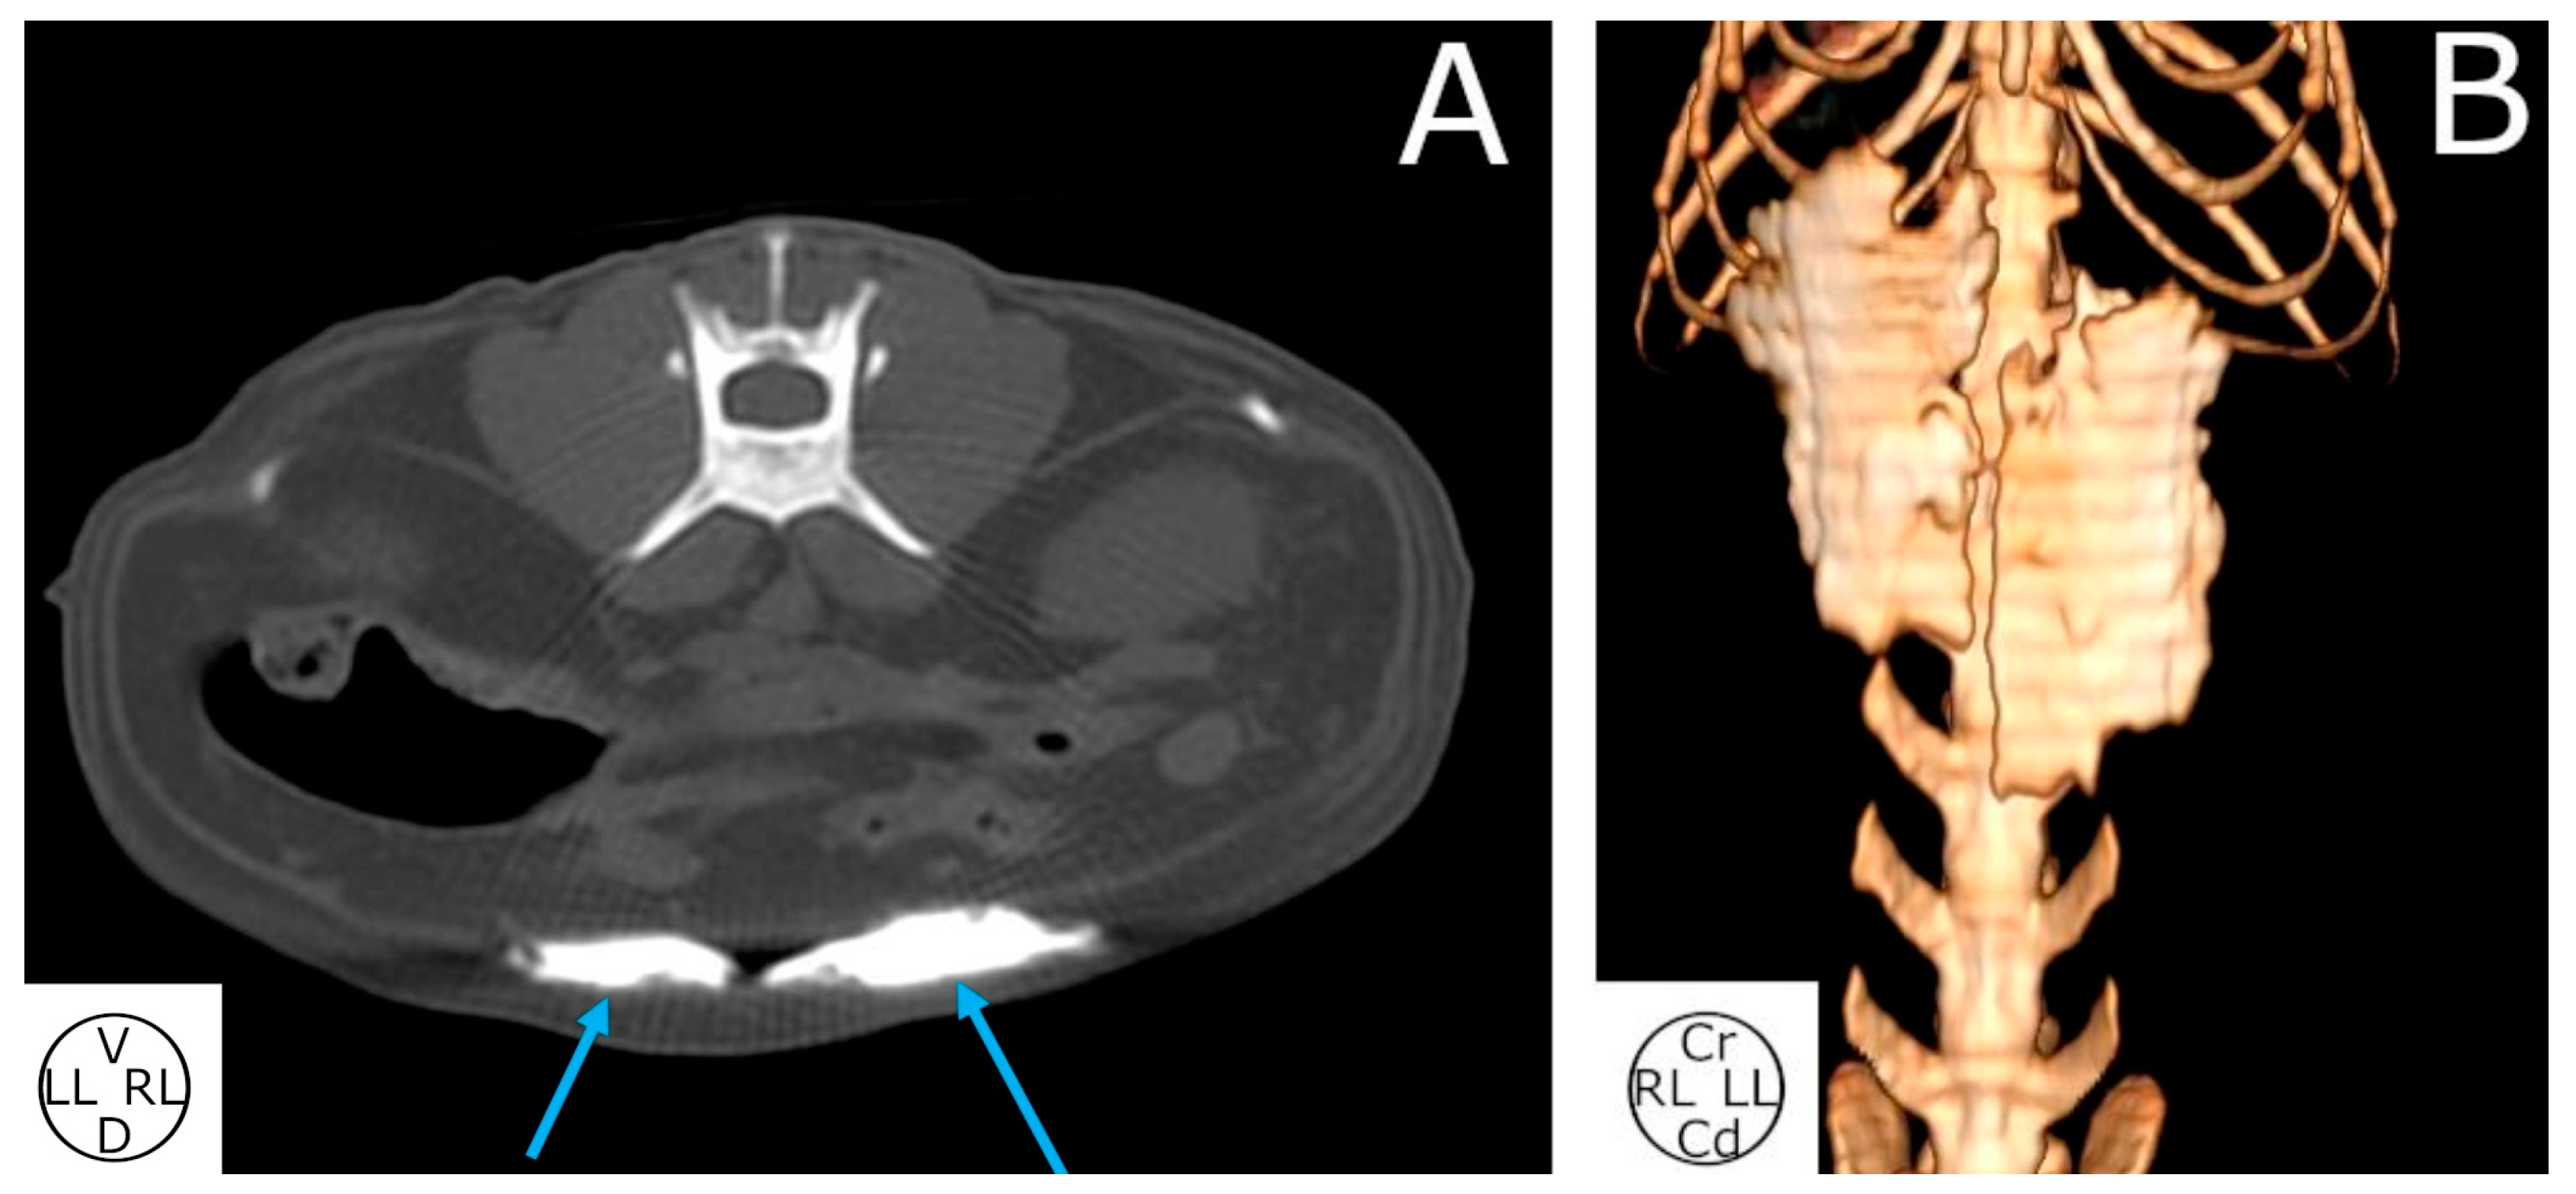

3.2.3. Computed Tomography Study

3.2.4. Spread Study